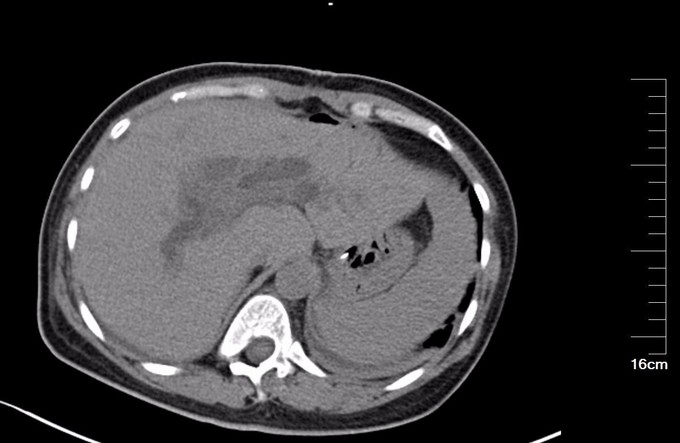

查体:腹部略膨隆,未见胃肠型及蠕动波,未见腹壁曲张静脉,右上腹部压痛阳性,无反跳痛或肌紧张,未及包块,肝脾肋下未及,Murphy氏征阳性,肝区扣痛阳性,肾区无扣痛,肠鸣音减弱,约4次/分,未闻及气过水声。 辅查: MR平扫+增强:肝脏大小形态未见异常,各叶比例正常,未见异常信号灶。肝内胆管、胆囊管及胆总管多发囊状扩张,胆总管直径6cm左右,壁厚且明显强化,腔内点状T2WI低信号影。胆囊饱满,其内可见聚集点状低信号影,胆囊壁增厚且明显强化。门脉血管显示清楚,走行正常。胰腺形态信号未见异常,胰管未见扩张。脾脏不大。增强扫描未见异常强化病灶。 MRCP:胆囊体积增大,肝内胆管、胆囊管及胆总管多发囊状扩张。胰管显影,形态走行未见异常。 CT 胆总管囊状扩张,囊壁较厚,前壁见点状钙化,较宽处直径约6.7cm,胆总管末端壁增厚,管腔狭窄;增强扫描扩张胆总管壁明显强化。肝内胆管扩张,胆囊增大,胆囊壁增厚、强化尚均匀,囊内未见异常密度影。 肝内未见异常密度影。胰腺形态、密度未见异常。脾不大。腹膜后未见确切肿大淋巴结影。